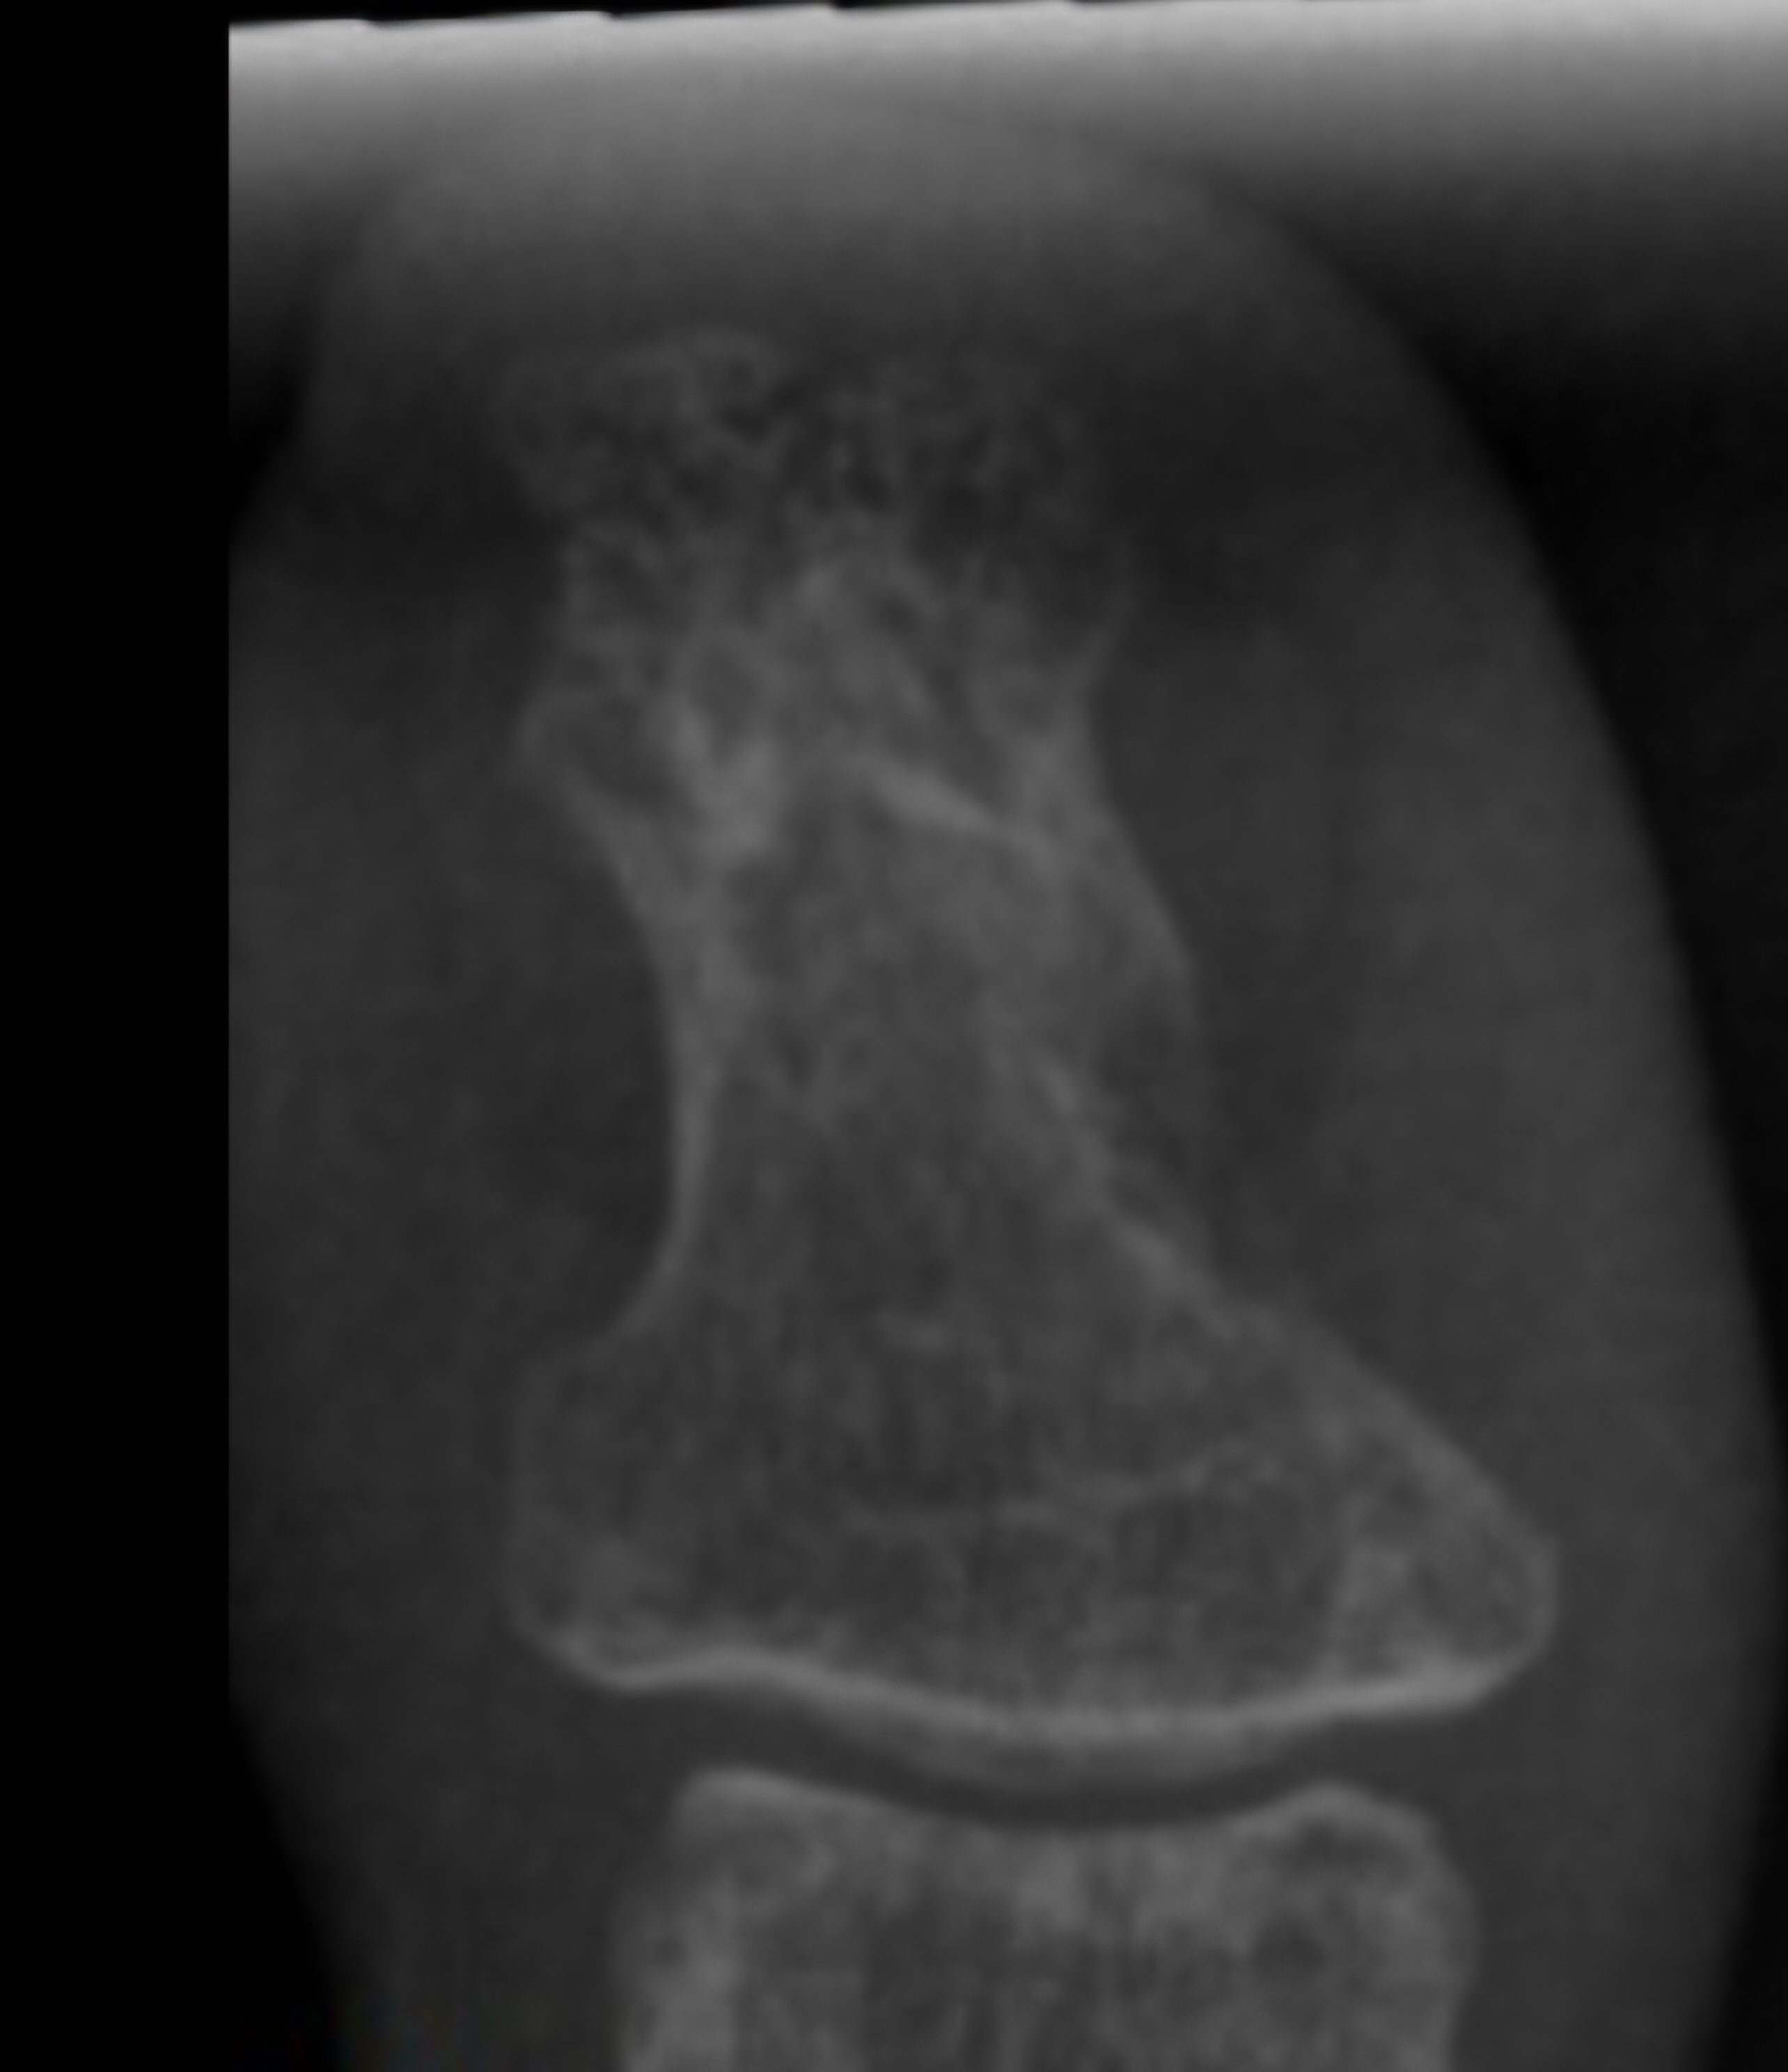

Patient was hospitalized in August 2022 for IV (Intravenous) metronidazole which helped reduce (but not eliminate) symptoms for about one month. MRI of the left toe showed still healing fracture and ortho consult did not recommend surgical intervention at that time. Multiple neurology consults were obtained to rule out neurological cause of symptoms given the unusual presentation and all neurology consults felt this was not primarily a neurological issue and she was referred back to Infectious Disease for management. EMG & MRI of the brain were done and were both normal. (Patient was advised to continue benzodiazepine during initial EMG so any possible exaggerated F-response and spasms were suppressed by benzodiazepines during the EMG). During all physical exams involuntary muscle spasms/ twitching of the left foot/toes were noted involving both agonist and antagonist muscles.

MRI one year after injury showed some abnormal signal. (Clostridium tetani infection generally has no clear radiological findings or lab confirmatory tests and is generally a clinical diagnosis). Patient sought consults with multiple infectious disease doctors in New York but despite repeated worsening off antibiotics, clear clinical signs of local tetanus in the left foot, progression of spasms / twitching up the left leg with generalization and autonomic symptoms including heart block and involuntary jaw closure within days of stopping antibiotics or walking more than small amounts, infectious disease physicians in New York (who have not had experience with tetanus) have been conflicted on the diagnosis and of little help. (The medical literature reports that the presentation of tetanus in an immunized patient would typically be different than the presentation in an unimmunized patient and instead of presenting with full body tetany, an immunized patient would present with an ascending pattern of spasms / twitching up the affected limb from the localized point of infection with progression to generalization as in this case.)

Patient sought surgical consult with a bone specialist surgeon who diagnosed patient clinically with tetanus osteomyelitis & surgical debridement of the left big toe (distal bone) was attempted 2 times. First surgery involved bone debridement of the medial side of the toe with placement of antibiotic laden calcium stimulan beads. The first surgery did not resolve the symptoms and actually worsened tetanus symptoms for about a month post surgery. One episode of brief full left leg tetany occurred in the first month post surgery . During the surgery, the surgeon visually graded the bone as "infected" with an infection level of 4 out of 4, stating the bone appeared much softer than it should be. (The surgeon specializes in bone surgery and stated he had never seen bone that looked like this) Cultures (anaerobic, aerobic and fungal) were negative but the surgeon and literature advises that anaerobic cultures rarely come back positive (accuracy is only about 30% in confirmed positive cases).